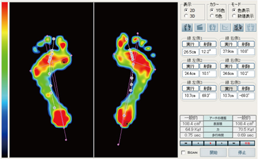

歩行検査

片方ずつの足でプレートを踏んで歩行し検査します。

圧力中心線の軌跡や歩行周期を動画で記録できます。

計測画面

足長、足幅、角度の計測が行えます。圧力中心線の軌跡から回内足、回外足等の歩行異常の分析が行えます。